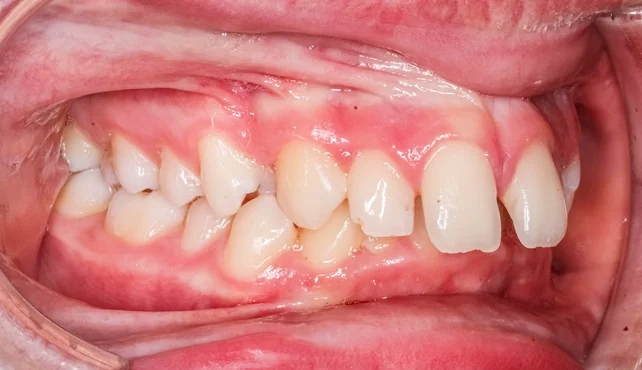

Clinical Features

Patients with increased overbite may present with:

- Excessive vertical overlap of upper incisors on the lowers (>4 mm).

- Minimal display of lower incisors on smiling.

- Palatal trauma from lower incisor impingement.

- Mandibular posturing or restriction of movement.

- Reduced lower anterior facial height and an acute nasolabial angle.

- Associated dental wear and gingival trauma.

Clinically, a distinction must be made between traumatic and non-traumatic deep bites.

- Traumatic deep bite: The lower incisors contact the palatal mucosa, often causing ulceration or recession.

- Non-traumatic deep bite: The overlap is increased but does not cause soft tissue injury.